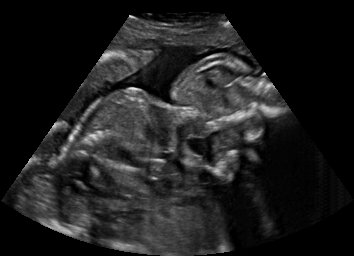

Real in-vivo images. 22 ultrasound sequences were collected using a GE Voluson E8 machine during standard fetal screening exams of 8 patients. Each sequence is several seconds long. We extracted all 4427 frames and resize them to , see Fig. 2 for some examples. The resulting image set was randomly split into training-validation-test sets by a 80-10-10% ratio.

Comparison to state-of-the-art. As seen qualitatively from the examples in Fig. 3, our method substantially outperforms the alternatives in terms of content preservation, while translating realistic US appearance. CycleGAN, SASAN, and CUT hallucinate inexistent tissue regions fail to generate fine anatomical structures, e.g. the ribs. StarGAN fails to generate faithful ultrasound speckle appearance, which leads to highly unrealistic images. Our method ConPres preserves anatomical structures, while enhancing the images with a realistic appearance. It further faithfully preserves acoustic shadows, even without explicit enforcement. However, as seen from the last column, the refraction artefact appears artificial in the images translated by all the methods. Note that although the imaging field-of-view (FoV) and probe opening in the simulation is significantly different from the real in-vivo images (Fig. 2) used for training, our ConPres maintains the input FoV closely compared to previous state-of-the-art. The results in Tab 2 quantitatively confirm the superiority of our method. Note that SSIM and FID/KID are used to measure translation performance from two different and sometimes competing aspects, with the former metric for quantifying structure preservation and the latter metrics for image realism.

A user study was performed with 18 participants (14 technical and 4 clinical ultrasound experts) to evaluate the realism of translated images for 20 US frames with example images shown in Figs. 3 and 4. For each frame, a separate questionaire window opened in a web interface, presenting the participants with six candidate images including the input simulated famre and its translated versions using CUT, CycleGAN, SASAN, StarGAN, and ConPres. As a reference for the given ultrasound machine appearance, we also showed a fixed set of 10 real in-vivo images. The participants were asked to rank the candidate images based on “their likelihood for being an image from this machine”. The average rank score is reported in Tab 2. Based on a paired Wilcoxon signed rank test, our method is significantly superior to any competing method (all p-values ).

Discussion. Note that, despite both being fetal images, the simulated and the real images have substantially different anatomical contents, which makes the translation task extremely challenging. Nevertheless, our proposed framework is able to generate images with appearance strikingly close to real images, with far superior realism than its competitors. Besides sim-to-real translation, given its multi-domain conditional nature, our proposed framework without any further training can also translate images between the other domains, e.g. seg-to-real or seg-to-sim, with examples presented in Fig. 5.